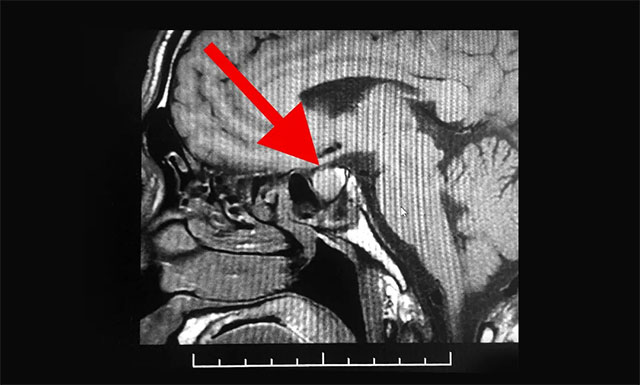

管先生因为咳嗽严重,于3月20日就诊于浙江省某医院,当时挂的是呼吸科,经过检查,医生说有些炎症,吃些咳嗽药就可以了。但与此同时,医生却发现管先生的鼻子、手部和指关节都要比常人大很多,遂建议他去脑外科检查,随后他在该医院又进行了头部MRI检查,根据影像检查结果,并结合其临床症状,患者最终被确诊为垂体瘤。

潘仁龙主任表示,患者容貌及四肢已发生很大改变,其四肢指关节粗大,声音嘶哑,结合其影像检查结果,手术指征明显,应尽早诊疗。